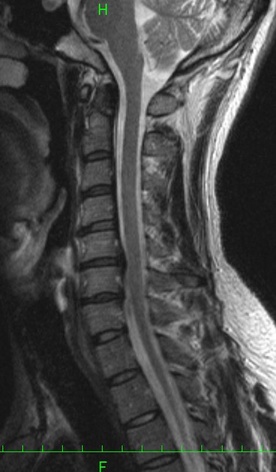

外傷性頚椎椎間板ヘルニアと診断を受けた画像

普通乗用車に乗車中、横転して受傷

C5/6に椎間板の後方突出の比較的大きなヘルニアが認められます。

頚椎の変性や他の椎間板に比して、同部位に明らかなヘルニアが認められることなどから、主治医は、外傷性の椎間板ヘルニアと診断しました。

主治医が医学的な根拠をもって、外傷性のヘルニア(本件事故により生じたヘルニア)と診断した場合、12級13号の認定の可能性は高まります。